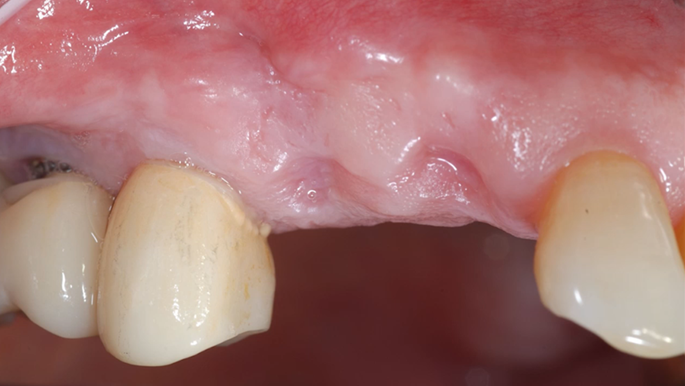

“Prefabricated provisional restorations can serve as custom healing abutments in case of insufficient initial stability for one-day implants. ”

Clinical case: Immediate implant placement using R2GATE Guide & custom healing abutment

- Courtesy of Dr. Sam Omar, Egypt -

Dr. Sam Omar, Digital Guided Surgery, Digital ONE-DAY Implant, Maxillary Posterior, #16, Guided surgery, Loading, Flapless, AnyRidge, R2GATE, MEGA ISQ, R2GATE Full surgical kit

Implant system-AnyRidge, R2 Guide, R2GATE Full Surgical Kit, Mega ISQ,